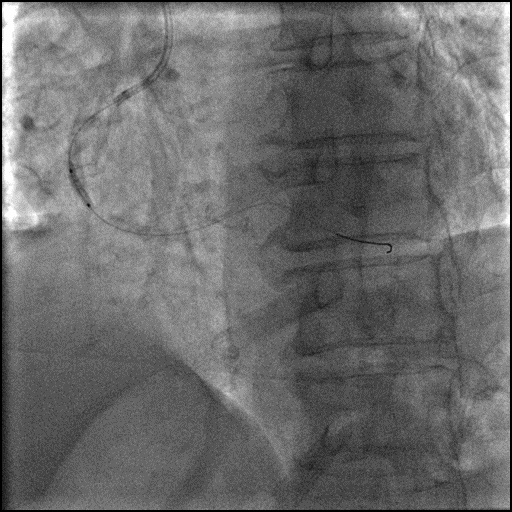

6F SAL1.0 GC, Finecross MGC,成功送入SION GW。

2.0x15mm, 2.5x12mm NC预扩张,球囊通过困难,改行旋磨术。

1.5mm 旋磨头 14万 RPM 旋磨6次。

6F Telescope™ 导引延长导管加强支撑。